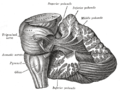

Upper surface of the cerebellum

Under surface of the cerebellum

Sagittal section of the cerebellum, near the junction of the vermis with the hemisphere

Dissection showing the projection fibers of the cerebellum